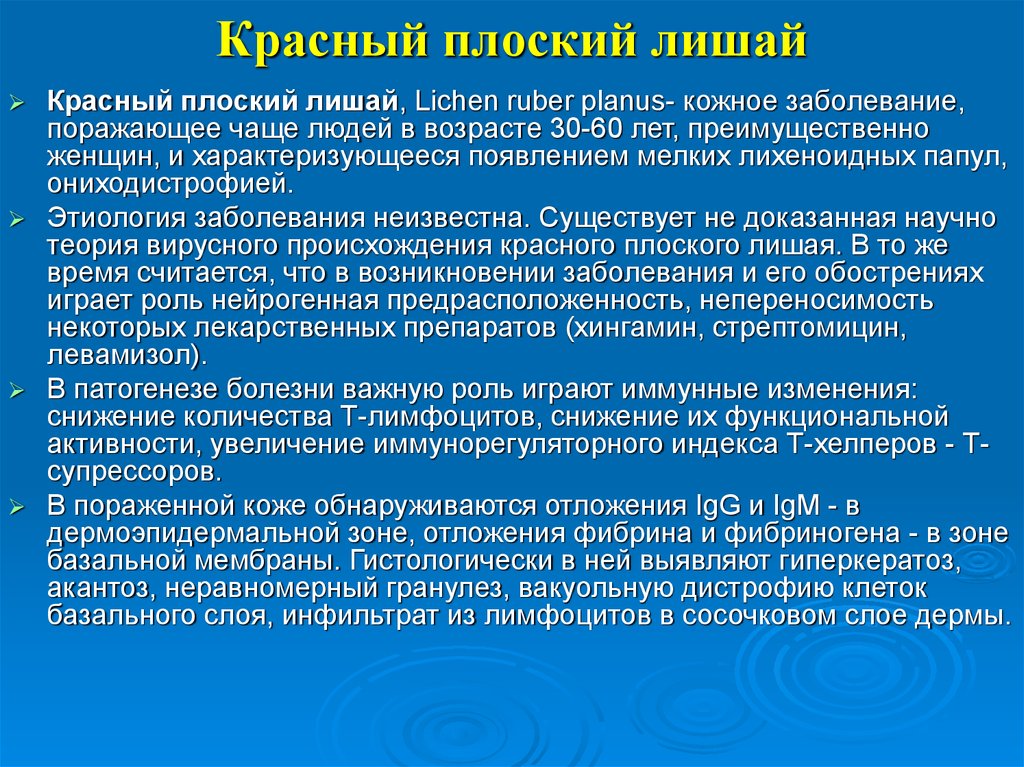

Фото Красного Плоского 103 фото